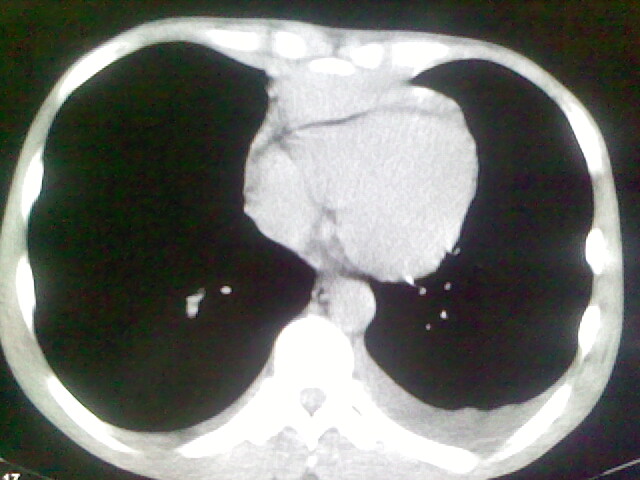

以下是引用杀毒软件在2008-9-3 6:11:00的发言:[br]侵袭性胸腺瘤------一般不侵到气管旁[br][br]考虑----纵隔淋巴瘤,心包及胸膜受累

以下是引用wzr在2008-9-3 5:30:00的发言:[br]侵袭性胸腺瘤

以下是引用随光逐影在2008-9-3 7:07:00的发言:[br]1)考虑淋巴瘤可能。2)双侧胸腔积液(以左侧为甚)。3)心包积液。